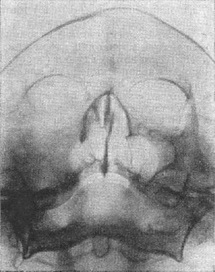

![]() Рис. 11. Саркома верхньої щелепи (ліворуч). Деструкція поширена на скуловую кістку і стінку очниці. Ліва верхньощелепна (гайморова) пазуха затемнена. |

При саркомі верхньої щелепи (рис. 11) руйнування кісткових елементів, выявляемому на рентгенограмах, супроводжує затемнення верхньощелепної пазухи і носової порожнини в результаті їх заповнення пухлинними масами. При остеогенної саркоми нижньої щелепи поблизу зон деструкції видно ділянки новоутвореної кістки у вигляді безформних і безладно розташованих склеротичних нашарувань. Кісткові включення і звапнення можуть бути видні і в самої пухлини.